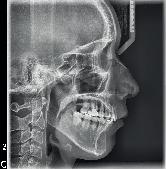

Figura 7. Lefort I. Figura 8. Osteotomía sagital. Figura 9. Mentoplastía. Figura 10. Cefálica de progreso. Figura 11. Panorámica de inicio.

Segunda fase quirúrgica de impactación maxilar Lefort I, 4 mm, (Figura 7), se realizó la cirugía mandibular que consistió en la osteotomía sagital de la rama bilateral de avance, 9 mm (Figura 8), se hizo la cirugía del mentón con la mentoplastía de avance 4 mm, (Figura 9) y una fase postquirúrgica de detallado y retención.

Fueron realizados después de 1 año y 2 meses de haber iniciado el tratamiento y después de la cirugía. En los estudios radiológicos tenemos que en la radiografía lateral de cráneo las placas utilizadas para consolidar la fijación de los maxilares, la corrección de las relaciones esqueléticas en la Figura 10. En la panorámica inicial se señalan los gérmenes de los terceros molares (Figura 11) y en la Figura 12, la realización de las exodoncias de órganos dentarios 18, 28, 38 y 48.